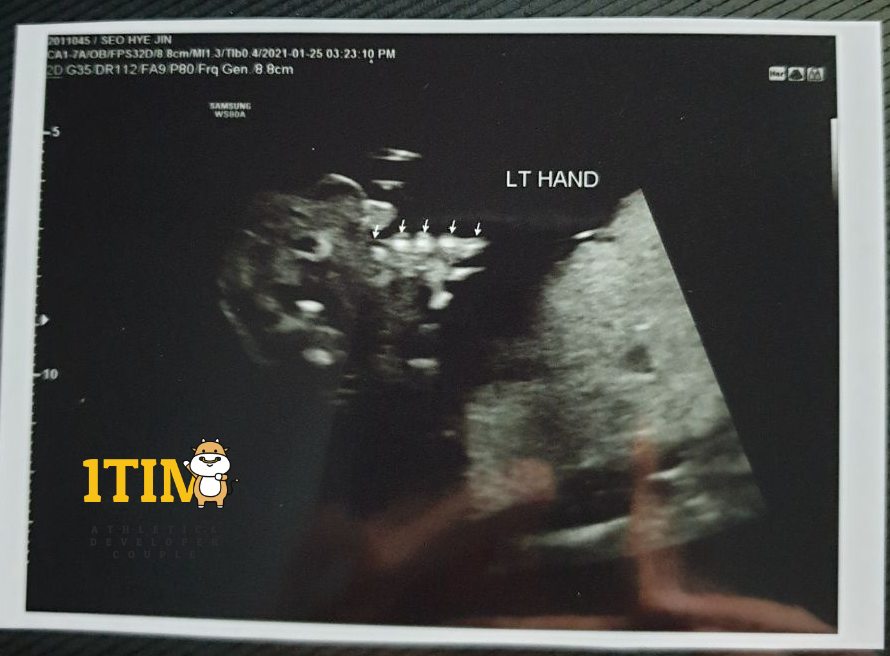

오늘은 한달만에 정기검진이 있는날. 정밀 초음파가 예정되어 있다.

양손가락/양발가락 갯수, 양쪽 귀, 입술, 코가 잘~~~ 붙어있는지 확인했다.

물론 정상 ~ 키키키 대견하구나.. 크롱군..